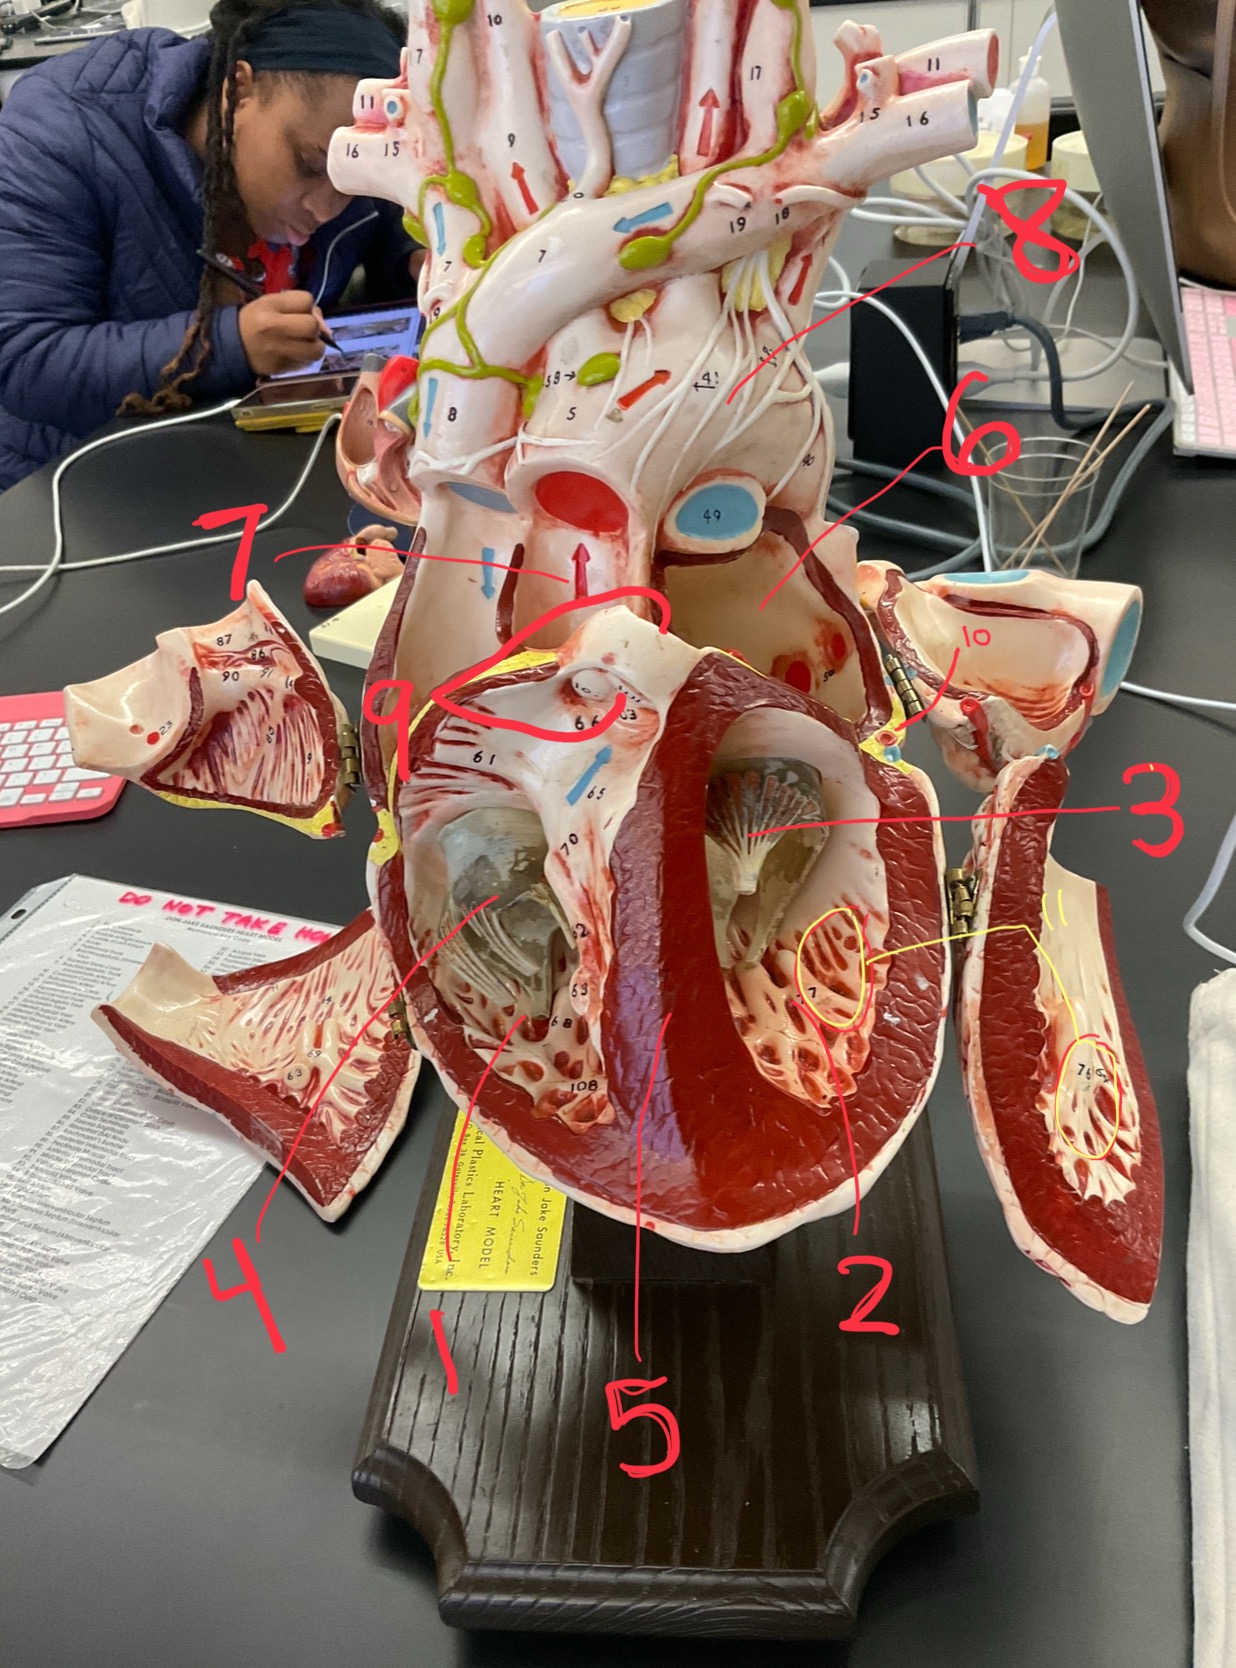

1

epicardium

2

3

endocardium

3

2

myocardium

4

1

coronary sinus

5

2

inferior vena cava

6

3

superior vena cava

7

1

right ventricle

8

2

left ventricle

9

3

bicuspid

10

4

tricuspid

11

5

interventricullar septum

12

6

left atrium

13

7

aorta

14

8

aortic trunk

15

9

pulmonary semi-lunar valve

16

10

atrevoventricullar sulus

17

11 (not smooth part)

trubeculae carneae

18

1

papillary muscle

19

2

chordae tendineae

20

4

pulmonary trunk

21

6

aortic trunk